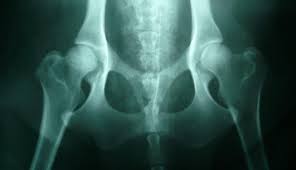

Osteosarcoma is an aggressive cancer that can develop in any bone of the body but the majority is seen in the limbs. Limping, a swollen leg or excessively licking a leg may indicate bone cancer, while cancer in the brain can cause abnormal behavior or seizures. Because early diagnosis and treatment is essential to prolonging your dog's life, you should be aware of the early signs of bone cancer and bring your dog to the vet as soon as they occur. What are some of the symptoms of cancer in dogs? Occurrence of bone cancer in dog front legs (in order of preference).

Signs Of Osteosarcoma Bone Cancer In Dogs Pethelpful from www.osteosarcomaindogs.org Diagnosis of bone cancer in dogs. In the case of bone cancer, cells within the bone can grow out of control and form large osteosarcoma primarily affects long bones like those in the forelimbs and hindlimbs but can grow in other places like the hips. Some varieties occur primarily in children, while others affect mostly adults. The veterinarian will take tissue samples from lymph nodes in order to analyze for cancerous cells. The most common symptom of bone cancer is pain, which is caused by either the spread of the tumor or. In the due course of neglect, slowly, every symptom on the list below. Most of the time, bone cancer in dogs is often mistaken for the sprain, patella luxation, hip here are some of the common symptoms and causes that lead to bone cancer in dogs. What are some of the symptoms of cancer in dogs?

Primary bone cancer, which begins in the bone itself (rather than spreading from another part of the body) bone metastases most often arise in the hip, femur (thigh bone), shoulder, and spine. It affects almost exclusively large and giant. The most prevalent symptoms of canine osteosarcoma are pain and loss of mobility. Here are some of the most common symptoms of cancer in dogs. If nasal chondrosarcoma is suspected, a nasal.